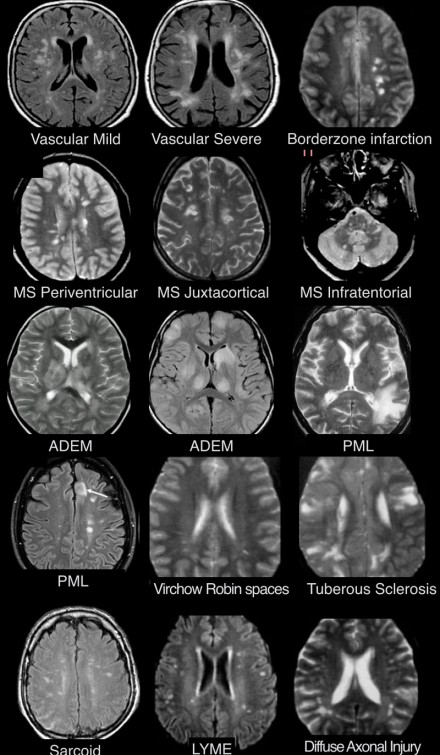

多發(fā)斑塊狀病灶的鑒別診斷

圖片一

在上圖中,是各種多發(fā)性點狀和斑塊狀白質(zhì)病灶圖像,我們對其中部分病例進行詳細討論。需要說明的是,以下鑒別診斷中提到的疾病與上圖中的圖像并不完全重合。

交界區(qū)腦梗死

MRI成像病灶要點:一般來說,這些病灶僅位于一個腦半球,要么位于深層白質(zhì)與灰質(zhì)的分水嶺區(qū)域(watershed area),要么位于周圍的分水嶺區(qū)域。在上圖中,病灶位于深層的分水嶺區(qū)域。

急性播散性腦脊髓炎(ADEM)

MRI成像病灶要點:在感染或接種疫苗后10-14天,多個局灶性病灶出現(xiàn)在腦白質(zhì)和基底節(jié)。與MS一樣,ADEM病變可累及脊髓、U形纖維以及胼胝體,有時可出現(xiàn)增強病灶。與MS所不同的是,ADEM的病灶通常更大,且好發(fā)于青年人,病程是單相的。

萊姆病

病灶大小約為2-3毫米,與MS的病灶相似,但患者會有皮疹和其他流感樣疾病。脊髓呈現(xiàn)高信號,CN7(神經(jīng)根入腦干區(qū))信號增強。

肉樣瘤

肉樣瘤的病灶分布與MS非常相似。

進行性多灶性白質(zhì)腦病(PML)

PML是一種由JC病毒感染引起的脫髓鞘性疾病,常見于免疫抑制患者。

MRI成像病灶要點:白質(zhì)損傷病灶在U形纖維的間隙占位,不增強,與HIV或CMV不同。

PML的病灶可在單側(cè)出現(xiàn),但更常見的是呈雙層、不對稱性分布。

血管周圍間隙(Virchow Robin spaces)

MRI成像病灶要點:T2加權(quán)成像明亮,F(xiàn)LAIR成像黑暗。

小血管性疾病

白質(zhì)損傷病灶位于深層白質(zhì)區(qū)域,不位于胼胝體、腦室旁或皮層旁。